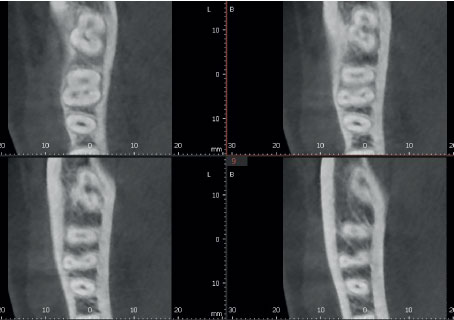

Режим Эндо с высочайшим разрешением

Режим Endo с объемом 4x4 см и размером вокселя 49,5 микрон оптимизирует обработку областей, представляющих повышенный интерес. Он идеально подходит для эндодонтии, поскольку стоматолог может получить изображение с высоким разрешением вокселей.